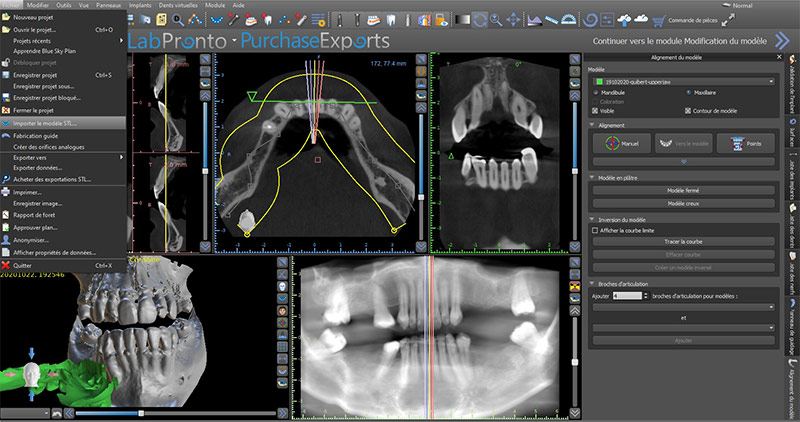

Fig. 02 : importation DICOM et sélection de la zone d’intérêt.

Importation des données STL et « matching »

Issus d’une empreinte optique en bouche ou d’une numérisation par un scanner de table, plusieurs fichiers STL peuvent être importés.

Pour ceci, aller sur l’onglet fichier, importer le modèle STL puis sélectionner le modèle STL souhaité.

Fig. 03 : importer le fichier STL.

Le matching consiste à superposer les données STL aux données DICOM. Il existe plusieurs méthodes pour réaliser la superposition : point par point, dent par dent ou automatique. Avec la nouvelle version, le matching se fait automatiquement de manière très précise.

Fig. 04 : le matching.

La fusion des images 3D et 2D est alors possible et réalisée. Pour vérifier le bon matching, nous vérifions si les contours du fichier STL se superposent correctement sur les contours des dents du dicom.

Fig. 05 : contrôle du matching.